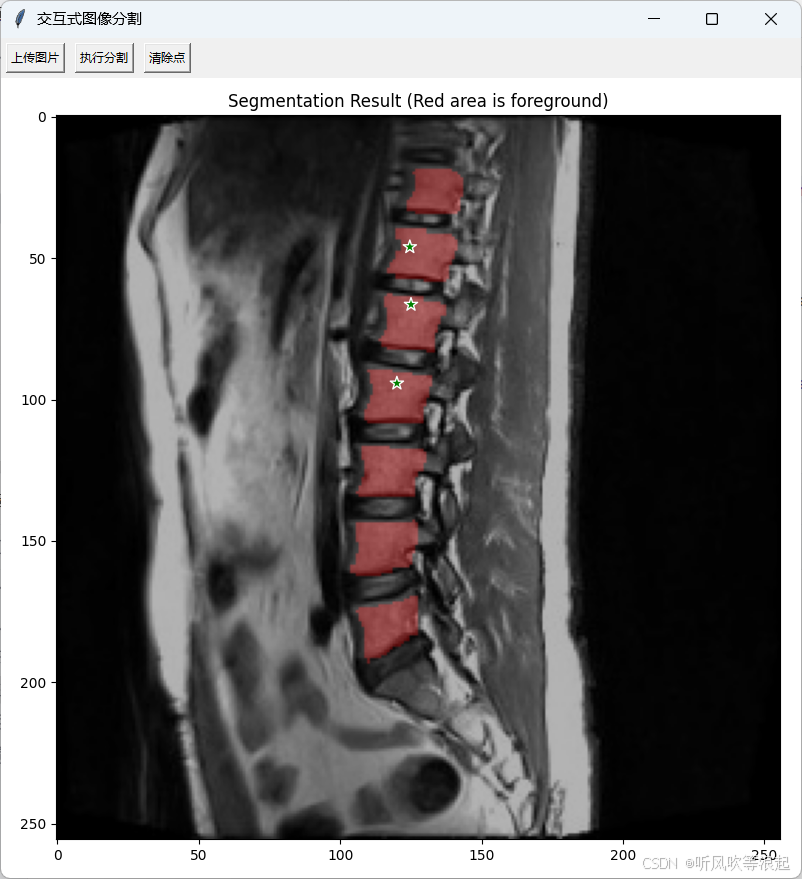

5. 交互式推理系统

基于Tkinter开发的GUI推理系统包含以下模块:

- 交互点选模块:左键添加前景点(绿色),右键添加背景点(蓝色)

- 结果可视化模块:将分割掩膜以红色半透明叠加层展示

用户上传图像 → 点击添加提示点 → 执行分割

→ 预处理(resize+归一化+点编码) → 模型前向传播

→ 后处理(resize回原尺寸) → 掩膜叠加显示